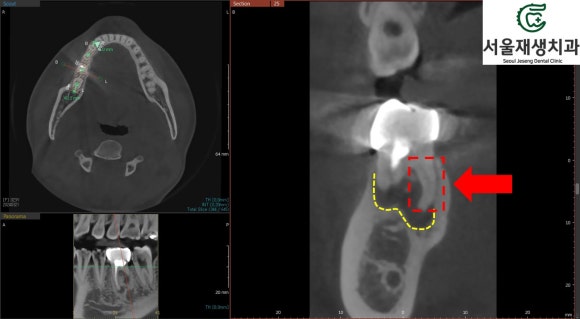

찾았습니다!

평면 엑스레이에서 의심되었던

'미치료 신경'의 위치를

CT를 통해 정확하게 파악합니다.

이제 남은 것은 미세현미경을 통한

꼼꼼한 재신경치료!